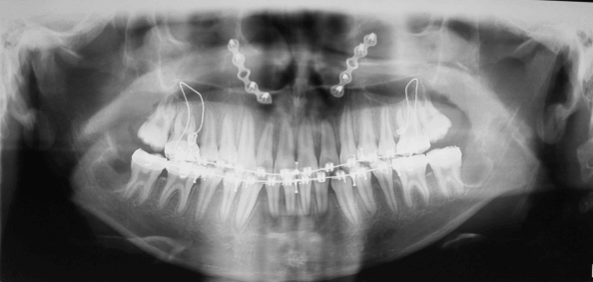

Fase Ortodoncia Post Quirúrgica y Finalización

En esta fase de Ortodoncia post quirúrgica donde se aprovecho el fenómeno de Aceleración Regional que se activa gracias a la cirugía ortognática y se lograron los objetivos oclusales, funcionales y estéticas en poco tiempo.